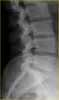

Osteopoikilosis

Osteopoikilosis is a benign, autosomal dominant sclerosing dysplasia of bone characterized by the presence of numerous bone islands in the skeleton. Presentation The radiographic appearance of osteopoikilosis on an X-ray is characterized by a pattern of numerous white densities of similar size spread throughout all the bones. [Source: Wikipedia ]